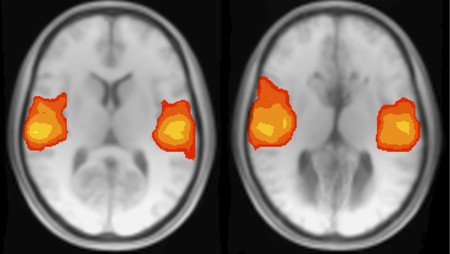

The Effects of Brain Defects

Tenzin Yin, a University of Florida senior double majoring in philosophy and interdisciplinary computational neuroscience, is researching brain activity in people with a birth defect called agenesis of the corpus callosum. The corpus callosum is a structure that connects the two hemispheres of the human brain.

Through the Amgen Scholars program, she is working in the lab of Ralph Adolphs, (PhD '92), Bren Professor of Psychology, Neuroscience, and Biology; Allen V. C. Davis and Lenabelle Davis Leadership Chair and director of the Caltech Brain Imaging Center